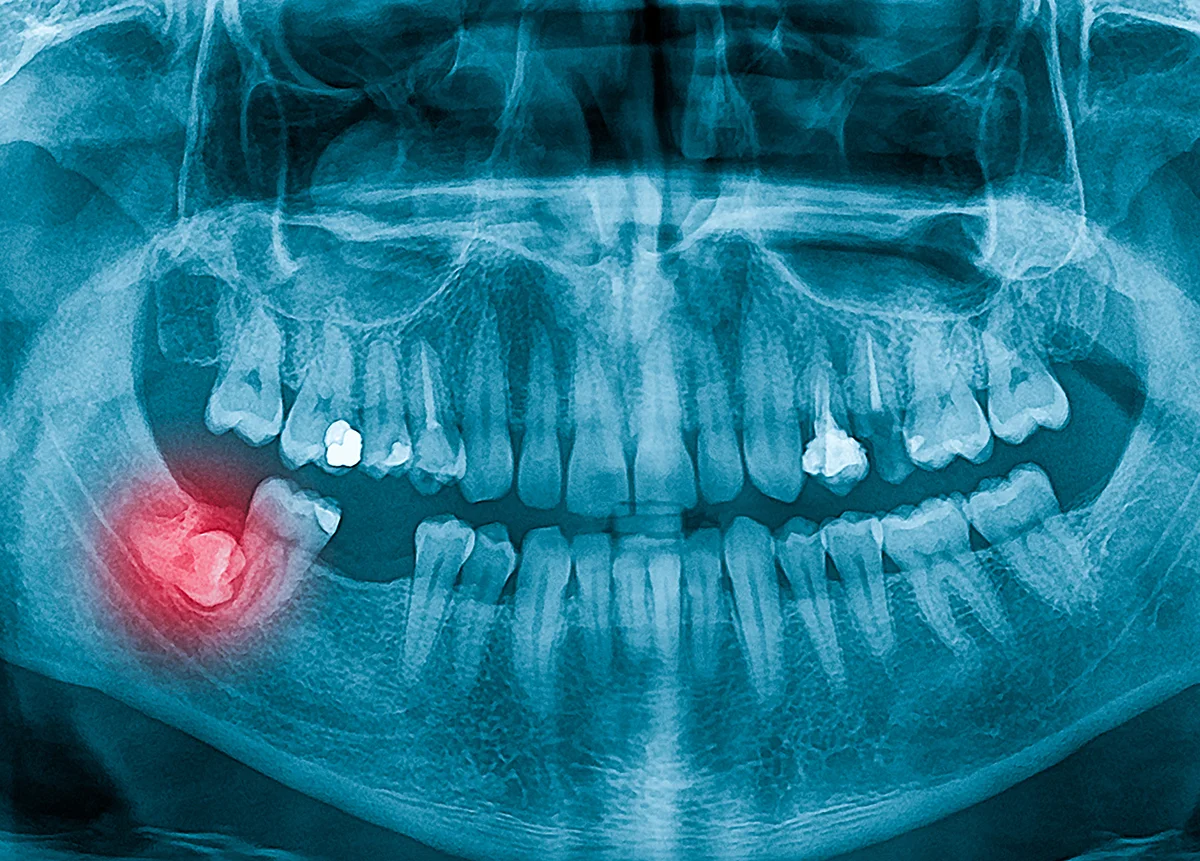

שיני בינה הן ארבע השיניים האחרונות שצומחות ומשלימות את כל 32 השיניים שישנן. אלה הן השיניים האחוריות ביותר כשהן יוצאות הן מהלסת העליונה והן מהתחתונה, אחת בכל צד. הן צומחות בגיל בוגר יותר משיניים אחרות, גיל 18-25 ומכאן שמן. לשיני בינה לא תמיד ישנו די מקום על מנת לצמוח כמו שצריך. כתוצאה מכך יכול להיווצר המצב של שן בינה כלואה, שן בינה שלא צצה בכלל או צצה באופן חלקי ביותר.

אבחון חד משמעי ניתן לעשות באמצעות צילום פנורמי כללי על האזור ואם נדרש גם צילום CT שיהיה ממוקד יותר ויאבחן את מצבה המדויק של כל שן.

הטיפול שניתן תלוי במידת הכליאה של השן, כלומר, האם היא כלואה לחלוטין או שכן צצה מעט. הוא גם תלוי במנח של השן: האם צמחה בכיוון אנכי וישר, מצב שהוא קל יותר לטיפול, או באלכסון עד כדי כיוון אופקי כמעט, מה שיחייב טיפול מורכב יותר.